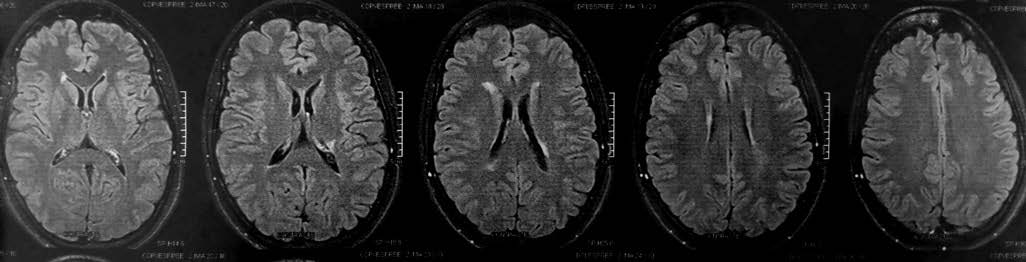

Seus sintomas são extremamente variáveis e dependem da localização e da gravidade de cada ataque inflamatório, chamado de surto. Podem ser: dormência, dor, formigamento, perda de equilíbrio e coordenação, dificuldade para caminhar, transtornos visuais, incontinência intestinal e urinária, diminuição da capacidade de atenção, perda de memória, transtornos fonoaudiólogos, cognitivos e emocionais, fadiga, entre outros. Ou seja, uma gama imensa de alterações motoras, sensitivas, visuais e cognitivas, que podem ser temporárias ou permanentes. O diagnóstico da doença é feito através de um exame clínico combinado com outros laboratoriais, que na maior parte das vezes serve para descartar outras doenças. Desses exames, o mais importante é a ressonância magnética, um exame que cria imagens de alta definição de órgãos internos através de um campo magnético.

Os pontos brilhantes das inflamações ativas.

Ao voltar à neurologista com o resultado da ressonância magnética, descobri que eu tinha inflamações ativas no cérebro, no cerebelo e na coluna cervical. Havia forte indicação de que eu tinha esclerose múltipla, mas ainda era preciso descartar seis outras possibilidades. A médica recomendou uma internação hospitalar no dia seguinte para realização de uma pulsoterapia com altas doses de um corticoide, a fim de conter o processo inflamatório. Em um primeiro momento, não entendi a gravidade do problema, os sintomas já tinham passado e eu me sentia bem. A médica precisou ser incisiva: as inflamações poderiam gerar sequelas irreversíveis.

Os exames não ficam mais fáceis ao longo dos anos. Mas pacientes desenvolvem estratégias para lidar com eles. Se nas primeiras experiências eu era surpreendida a cada novo procedimento, nos anos seguintes eu escolhia até aonde iria com as investigações. Para as ressonâncias magnéticas, que após o diagnóstico chegaram a durar mais de duas horas, por exemplo, passei a ir acompanhada e tomar um ansiolítico para suportar, imóvel, o tempo dentro da máquina. A indicação de novos remédios para conter os efeitos de outros, ou de exames, era uma prática recorrente nas consultas médicas realizadas.